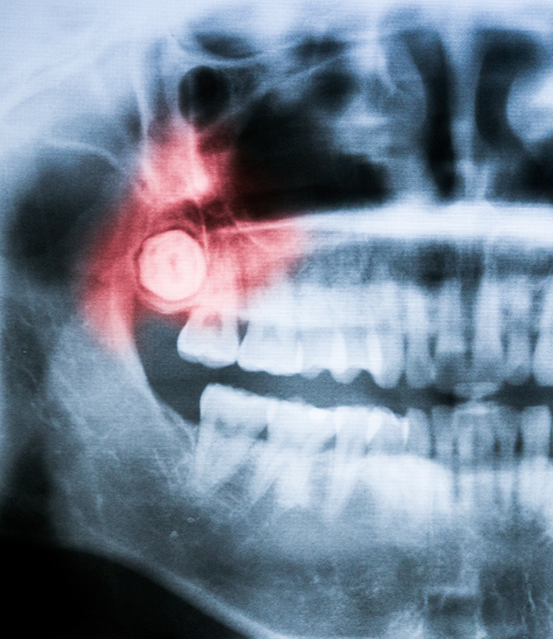

Titanium Dental of Fort Worth uses modern imaging and diagnostics to assess if this dental procedure is necessary. We will choose the best course of action for your smile.

At Titanium Dental of Fort Worth, your comfort and safety are our top priority. We use CT scanning to get a detailed 3D image of your jaw. This helps us:

- Identify the exact location of your wisdom teeth

- Evaluate how close the roots are to your nerves and sinuses.

- Plan the most efficient wisdom teeth removal.